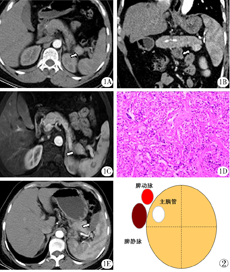

例1,女性,44岁。因"反复发作性出汗、心慌、乏力4年余"入院。无心、肺、肾等重要脏器疾病史,查体无阳性体征。随机末梢血血糖2.4 mmol/L;空腹血糖1.73 mmol/L;糖化血红蛋白3.30%;空腹血清胰岛素372.63 mU/L。增强CT见胰尾部类圆形等密度结节,动脉前期、动脉期明显强化,强化幅度高于正常胰腺组织,大小1.8 cm×1.7 cm,边缘清晰(图1A)。静脉及延迟期强化幅度略高于正常胰腺,冠状位重建示胰尾部肿瘤向下方生长(图1B)。增强MRI扫描见胰尾部类圆形结节,边缘清,T1WI压脂为低信号,T2WI为略高信号,增强扫描呈均匀强化(图1C)。结合临床,考虑胰岛素瘤。

2015年9月12日,患者在全麻下行腹腔镜下胰岛素瘤射频消融术。打开胃结肠韧带,显露胰体尾,于胰尾末端见一直径约2.0 cm瘤体。钳取约0.5 cm的瘤体组织送病理检查。快速冰冻结果提示为良性,遂决定行胰尾肿瘤RFA治疗。术中血糖为2.4 mmol/L。在腹腔镜引导下,将Cool-tip ACTC 2020射频针经皮肤穿刺入腹腔,直视下穿刺瘤体,多点消融瘤体。射频发生器采用Covidien Healthcare产品(爱尔兰,都柏林),射频功率设定在40 W以下。RFA后血糖逐步升为3.9 mmol/L。消融区置引流管一根。术后安返病房。术后无出汗、心慌、乏力等症状发作。空腹血糖5.26 mmol/L,随机末梢血糖5.73 mmol/L,糖化血红蛋白:4.30%,血清胰岛素:63.38 mU/L。

术后72小时拔除引流管,无胰漏发生。术后7天出院。术后病理报告:胰腺神经内分泌肿瘤,G1(图1D)。术后9个月随访,患者生活质量好,无出汗、心慌、乏力等症状发作。增强CT示胰尾部肿瘤完全消融,局部有少量液体积聚(图1E)。

主胰管多位于胰腺的后上方,主胰管的偏位为胰岛素瘤的RFA治疗提供了更多的安全保障。从胰腺断面看(图2),胰管常位于胰腺的后上方,与胰动静脉毗邻,胰腺上半部的前1/2和下半部分是RFA治疗的安全区域。另外,胰尾是主胰管的盲端。在主胰管通畅的前提下,如果在胰尾区域发生主胰管的穿刺损伤或热损伤,理论上不会发生顽固性胰漏。所以,整个胰尾都是RFA的安全部位。